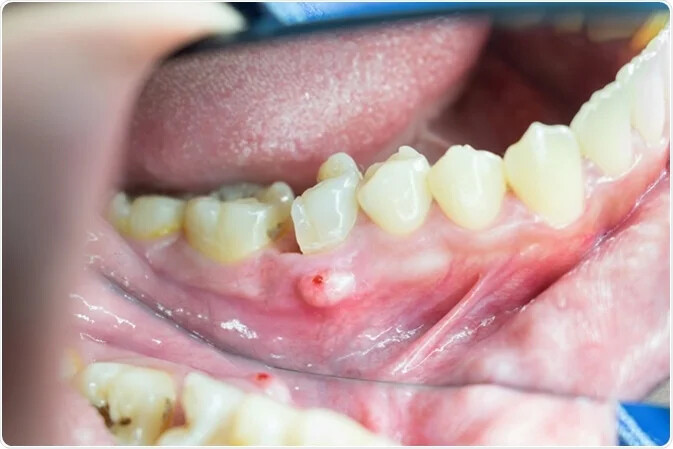

Apical Periodontitis: Causes, Symptoms, and Treatments

A healthy smile involves more than just strong, shiny teeth. Your gums also play an important role in your oral health, and some forms of gum disease can be pretty sneaky. Apical periodontitis, also known as periapical periodontitis, does not always have symptoms but should not be ignored. Find out more about periapical periodontitis and its causes, symptoms, and treatments.

Apical periodontitis refers to the inflammation of the periodontium — the tissue that surrounds your teeth. Apical means "relating to the apex," so inflammation usually occurs around the tip — or apex — of the tooth's root. Two types of apical periodontitis exist:

Typically, apical periodontitis occurs when there's another problem with the tooth. For example, inflammation can develop if a person has an untreated cavity. In some cases, apical periodontitis can develop if the pulp of the tooth becomes infected or dies. Injury or trauma to the tooth can also lead to apical periodontitis.